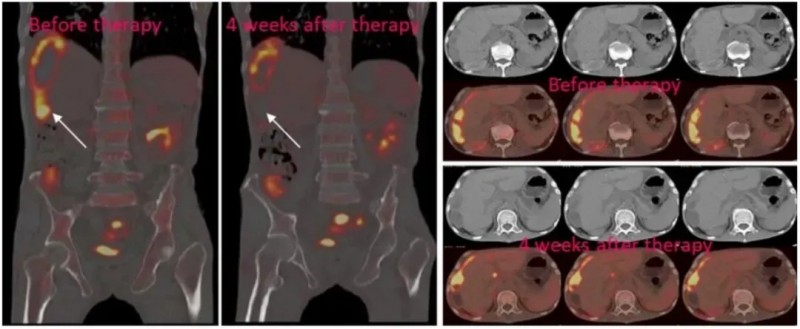

广州医科大学一篇2020年的硕士论文披露了NKG2D mRNA CAR-NK细胞疗法治疗转移性结直肠癌的临床研究成果。该研究以局部输注方式,对3例患者开展了靶向NKG2D的CAR-NK细胞治疗。

结果显示:2例患者经腹腔输注低剂量CAR-NK细胞后,腹水生成速度显著减缓,腹水中的肿瘤细胞数量急剧下降;另1例伴肝转移的患者采用“腹腔灌注联合超声引导下瘤内注射”方案治疗后,PET-CT检查提示肝脏病灶实现完全代谢缓解(详见下图)。值得关注的是,3例患者在治疗全程均未出现3级及以上不良反应。

该研究初步证实了NKG2D mRNA CAR-NK细胞用于转移性结直肠癌治疗的安全性与可行性,为晚期患者开辟了免疫治疗新路径。

▼3号患者经NKG2D CAR-NK治疗后,肝转移病灶的PEC-CT对比